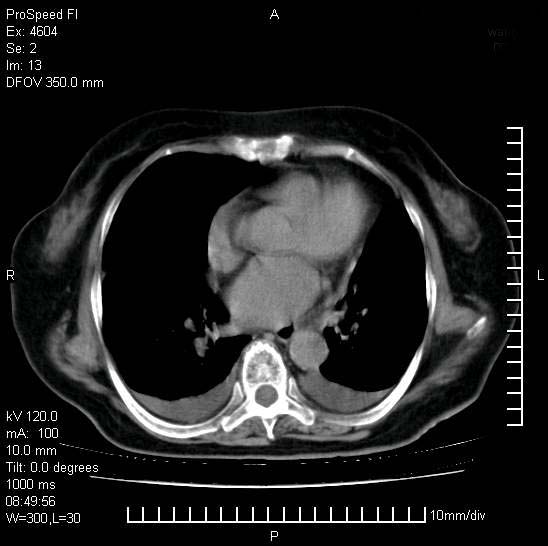

十几年前曾患肺结核,一周前突咳血约100ml,中性粒细胞稍高,诊断两上肺陈旧结核,下肺炎症,给予抗炎治疗,近几日晚上高热,39度,仍咳少量血,4天前ct及今天ct上传。

今天ct

短短几天内,病变范围明显增多扩大,以左侧明显,而且双侧出现胸水,还是考虑感染.